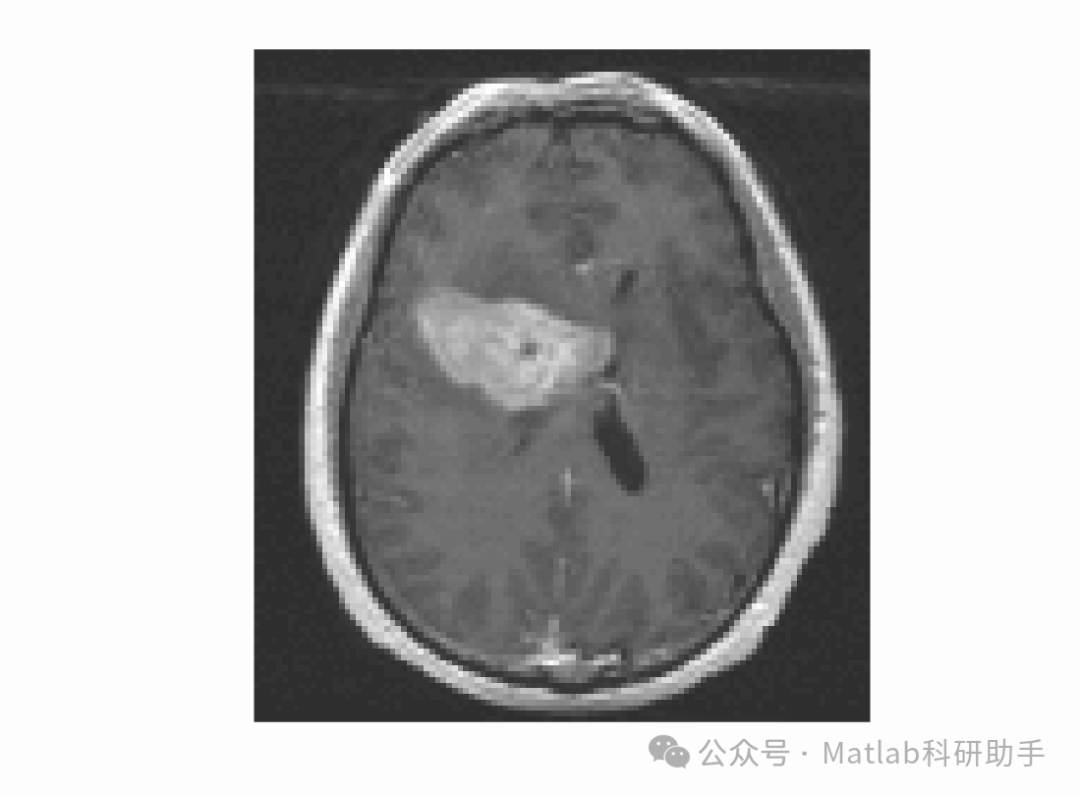

主动轮廓模型(Active Contour Model,ACM)作为一种自适应分割方法,通过构建能量函数引导曲线逐步收敛到目标边界,有效克服了传统算法对噪声敏感、依赖人工干预的缺陷,在医学影像(如肿瘤分割、器官提取)、遥感图像(如地物分类)等领域展现出显著优势。主动轮廓模型主要分为基于边缘和基于区域两类:基于边缘的模型(如 Snake 模型)依赖图像梯度信息,对弱边界和灰度不均匀图像分割效果较差;基于区域的模型(如 CV 模型)利用区域灰度统计信息,对灰度不均匀图像的适应性有所提升,但多采用全局灰度分布假设,难以准确描述图像局部灰度变化,在处理复杂纹理或强噪声图像时易出现轮廓泄漏、分割不准确等问题。

针对上述不足,本研究提出一种由局部高斯分布拟合能量驱动的变分水平集活动轮廓模型。该模型通过引入局部高斯分布拟合(Local Gaussian Distribution Fitting,LGDF)能量,充分利用图像局部区域的灰度统计特性,更精准地刻画图像局部灰度不均匀性;同时采用变分水平集方法表示活动轮廓,避免传统参数化模型拓扑结构固定的局限,实现对复杂形状目标的灵活分割。此研究不仅能够提升复杂图像的分割精度与鲁棒性,还能为医学诊断、工业质检等实际应用提供更可靠的技术支撑,具有重要的理论创新价值与实际应用前景。

本研究提出的由局部高斯分布拟合能量驱动的变分水平集活动轮廓模型,通过充分利用图像局部灰度统计特性,有效解决了传统基于区域模型对灰度不均匀、复杂纹理图像分割效果差的问题,主要结论如下:

- 模型通过构建局部高斯分布拟合能量,联合利用局部灰度均值与方差信息,比仅考虑局部均值的 LBF 模型和 LGDF(简化版)更精准地刻画图像局部灰度变化,显著提升了灰度不均匀图像的分割精度。

- 采用变分水平集方法表示活动轮廓,结合正则化能量保持水平集函数的稳定性,实现了对复杂拓扑结构目标(如多肿瘤、多缺陷)的灵活分割,克服了参数化模型的局限性。

- 实验结果表明,在医学影像、自然图像、工业缺陷图像分割任务中,模型的 DSC、IoU 均优于 CV 模型、LBF 模型和 LGDF(简化版),HD 显著降低,虽运行时间略长,但满足多数实际应用场景的效率需求。